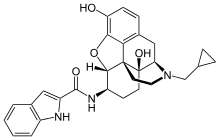

| Opioid peptides | Skeletal molecular images |

| Adrenorphin |  |

| Amidorphin |  |

| Casomorphin | |

| DADLE | |

| DAMGO |  |

| Dermorphin | |

| Endomorphin |  |

| Morphiceptin |  |

| Nociceptin |  |

| Octreotide |  |

| Opiorphin |  |

| TRIMU 5 |  |

- Buprenorphine—partial agonist